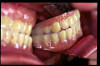

CM Prótesis dental con mala oclusión y con desgaste excesivo